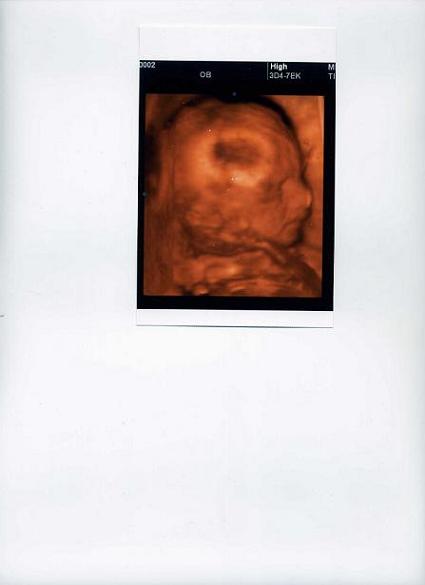

zuzmi örülök, hogy kisfiatok lesz! örülök, hogy minden rendben van a vele, nagyon cuki kis krapek.

az én lepényem is elöl fent tapad, és az én kicsikém is az arca elé pakolta a kezeit meg lábait.

remélem a 4 D-n jó kislány lesz.